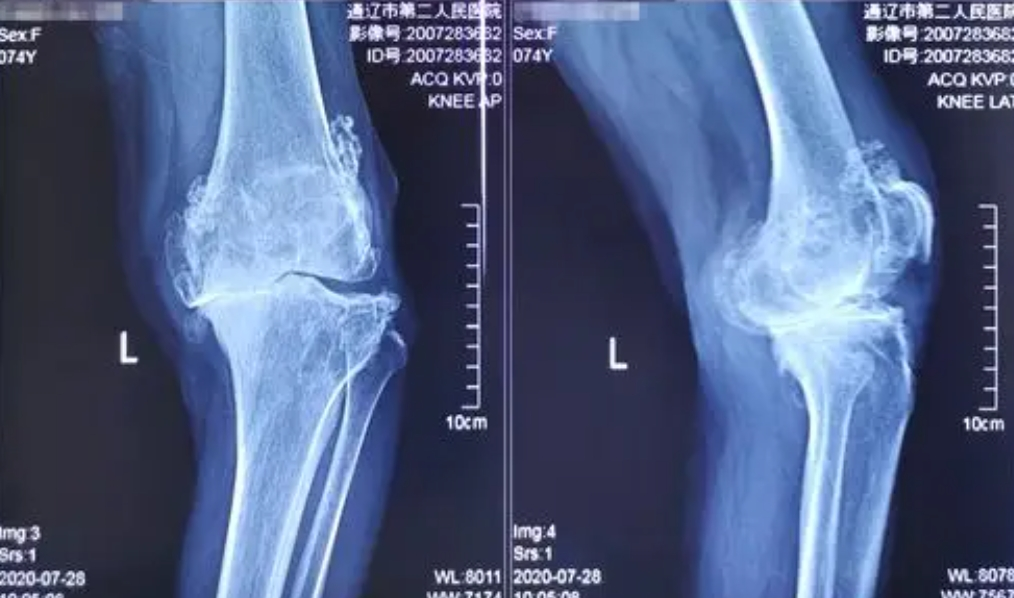

2、骨质增生(骨刺):软骨磨损后,骨头边缘为增加稳定性而代偿性增生(起初是良性增生),形成骨赘(骨刺),进一步刺激周围组织引发疼痛。

忽视早期的代价是沉重的:当疾病进展到中晚期(软骨大面积磨损或剥脱、骨刺大量增生、关节严重变形),疼痛持续剧烈、关节活动度显著受限(无法伸直或弯曲)、跛行甚至影响睡眠。此时保守治疗往往杯水车薪,关节镜清理术效果有限且不持久,最终多数患者不得不面临创伤大、费用高、恢复期长的全膝关节置换术。